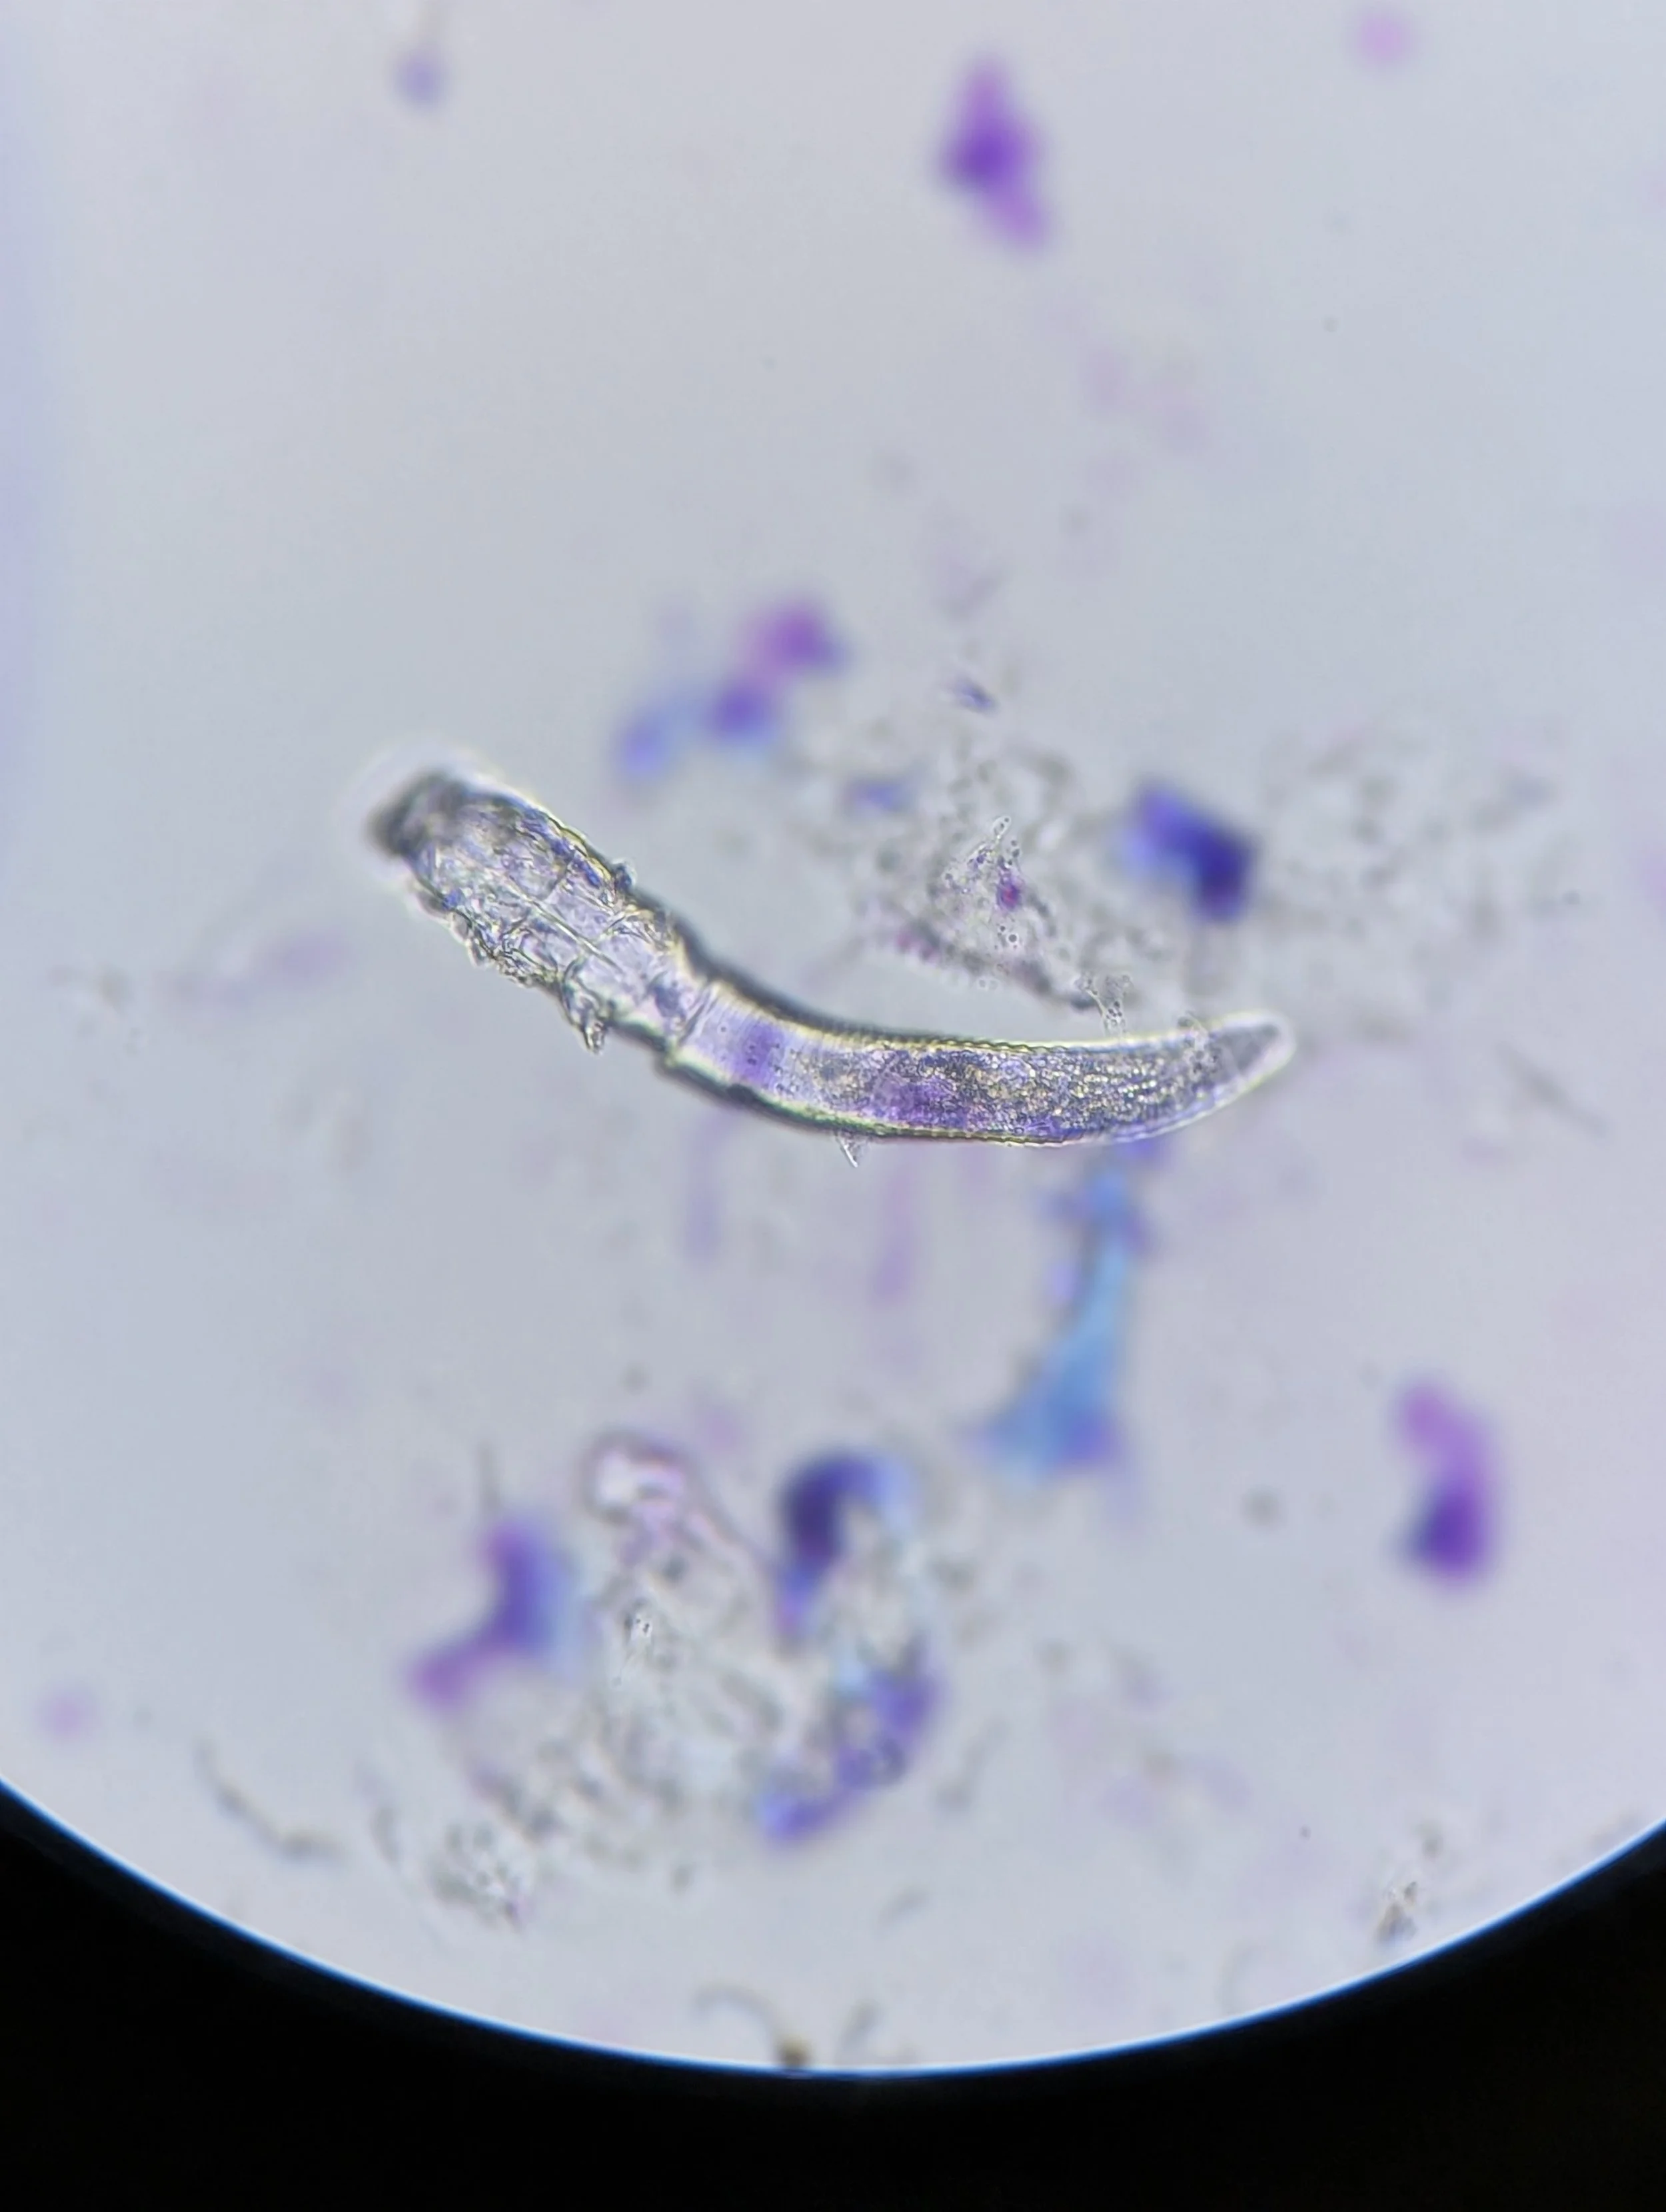

Demodex found during ear cytology. This ectoparasite usually lives in hair follicles, including in human eyelashes, and is a type of mite